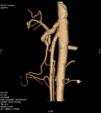

Se realizó una TC abdominal en la que se identificó una pinza aortomesentérica superior de 19° con dilatación y volvulación del duodeno proximal (figs. 1 y 2).